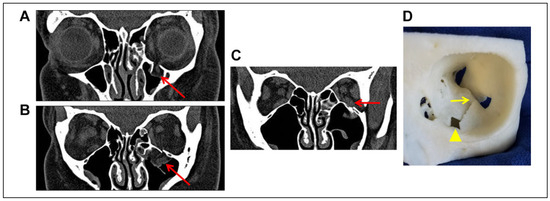

Case Report